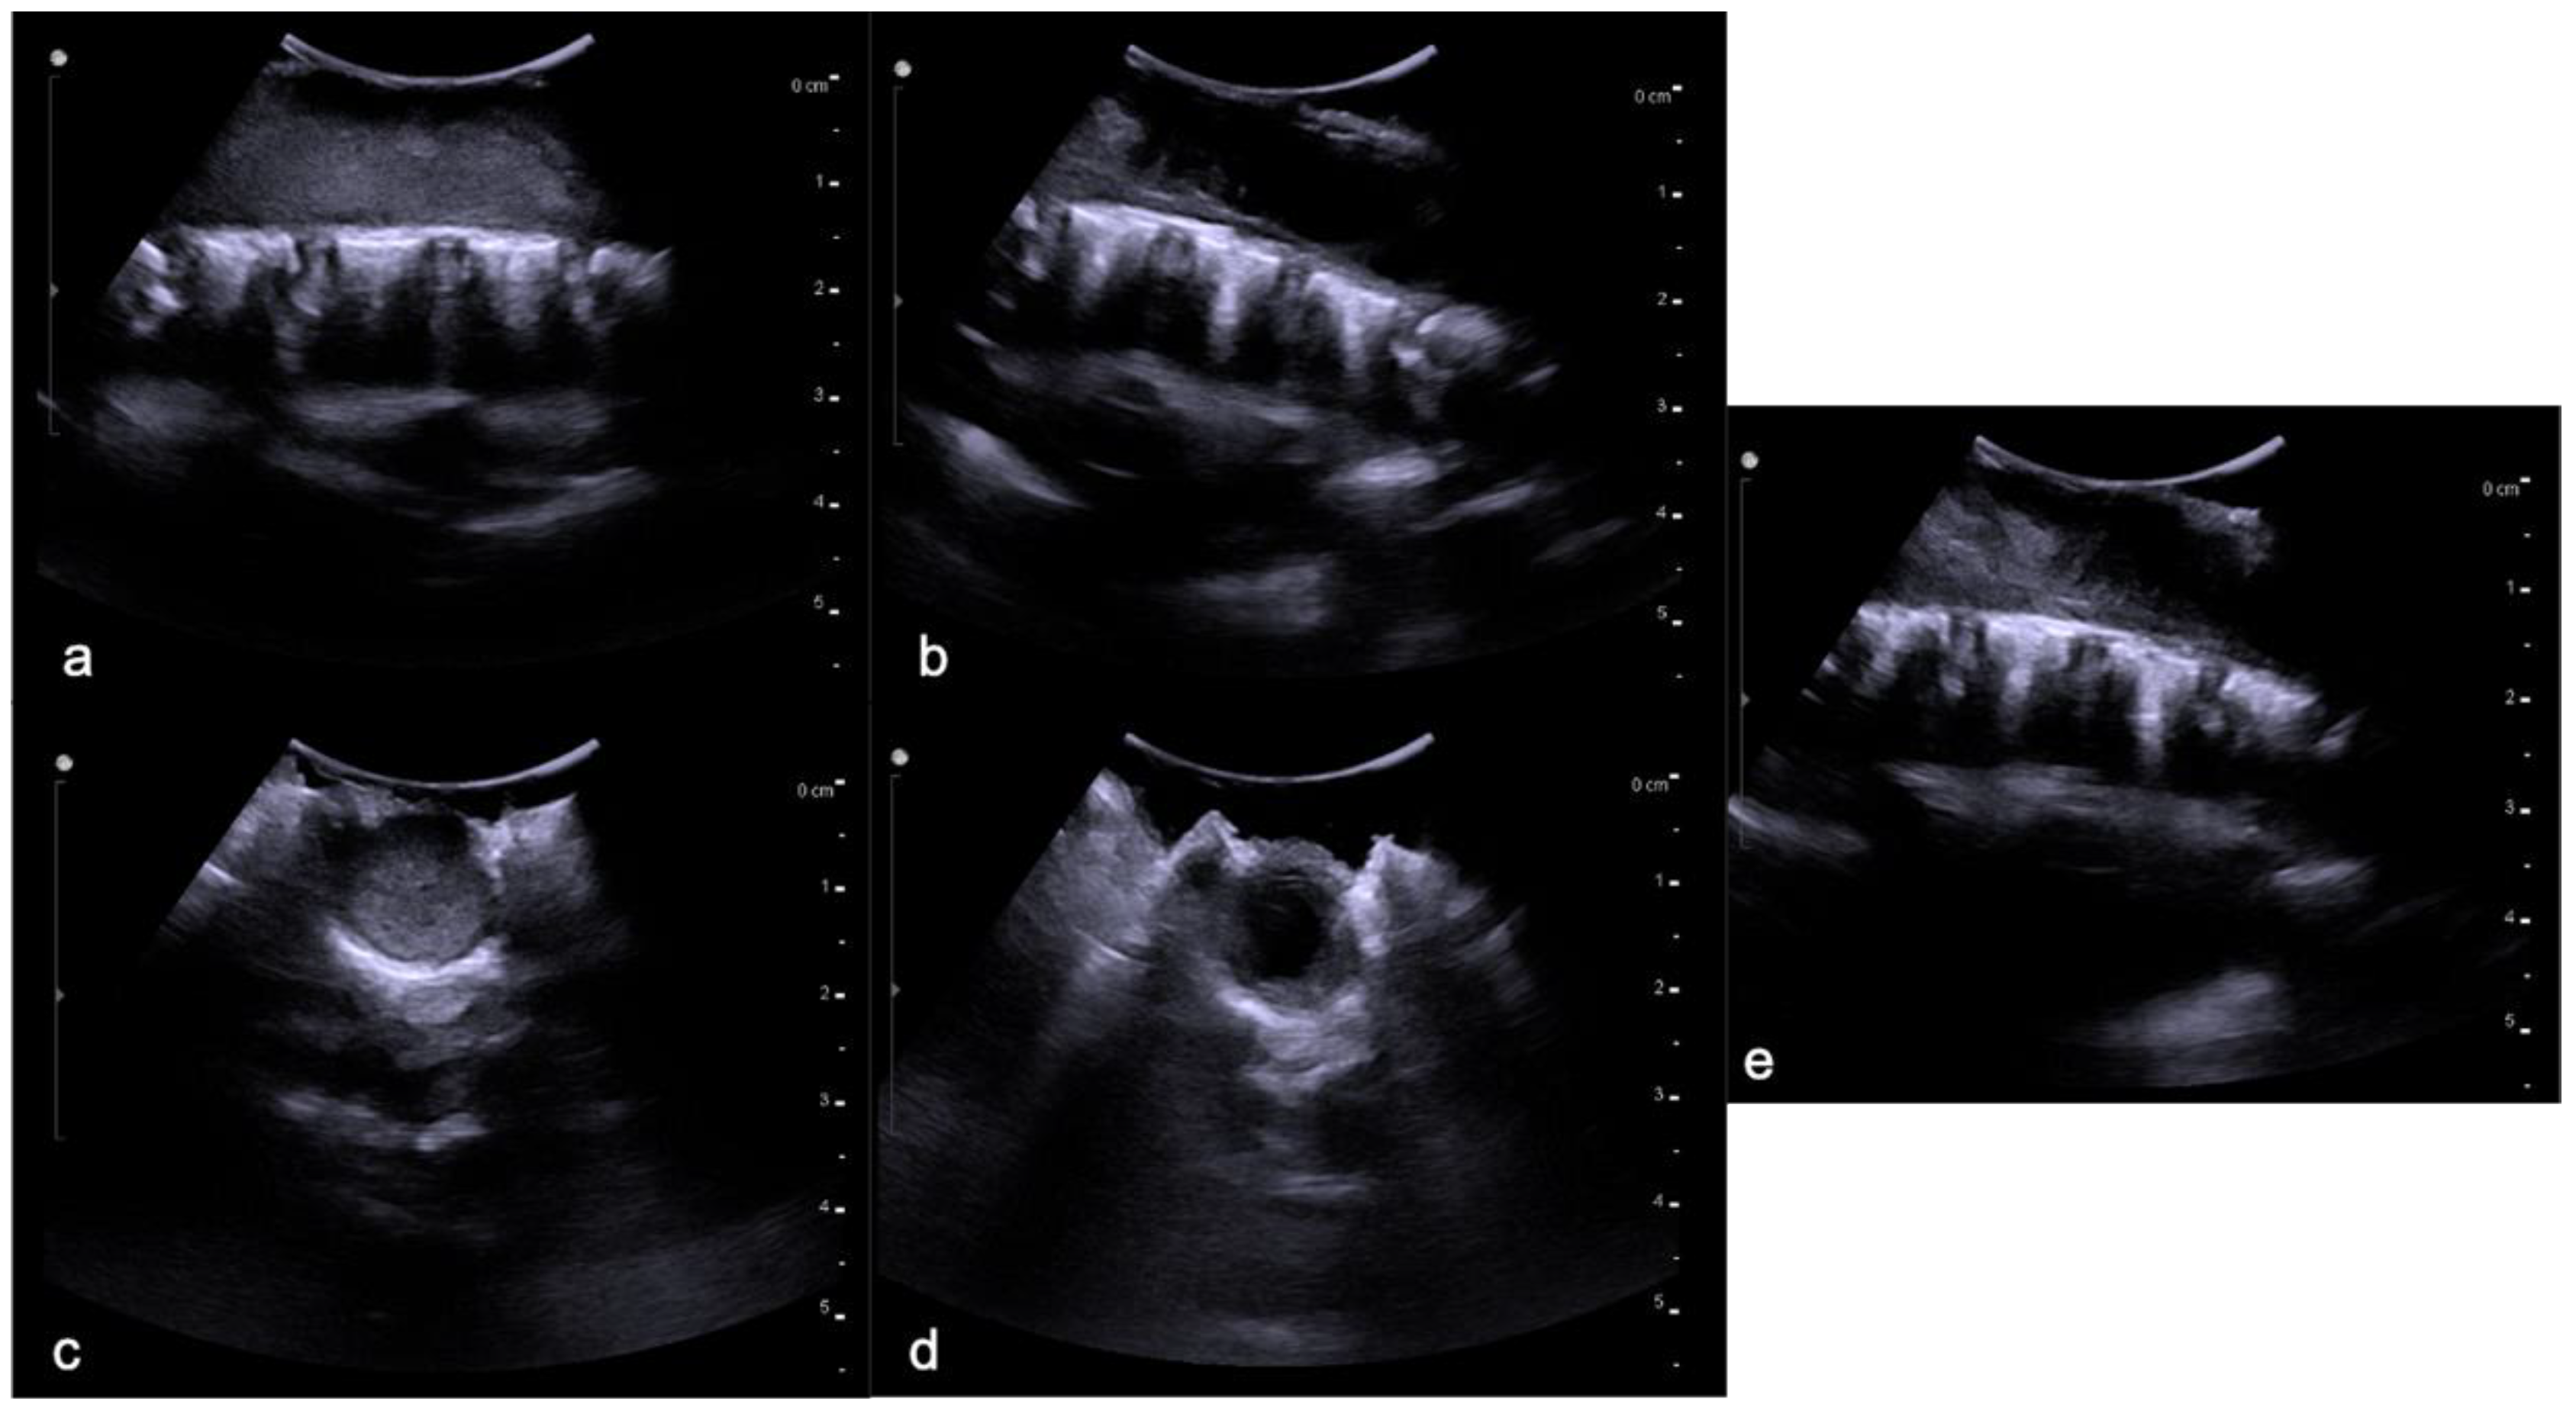

4.1. Hemangioblastomas

- Gläsker, S.; Vergauwen, E.; Koch, C.A.; Kutikov, A.; Vortmeyer, A.O. Von Hippel-Lindau Disease: Current challenges and future prospects. OncoTargets Ther. 2020, 13, 5669–5690. [Google Scholar] [CrossRef] [PubMed]